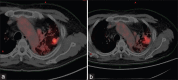

This is a case report of a 60-year-old diabetic, hypertensive male with a good performance status and a history of bilateral interstitial lung disease with a left upper lobe lung mass diagnosed to be a Stage IIB mixed small-cell/squamous cell carcinoma which was refractory to carboplatin- and etoposide-based chemotherapy. The patient was then taken up for adaptive intensity-modulated radiotherapy with tighter margin under image guidance with a mid-treatment replanning done at 25#. Acute toxicities were assessed weekly and showed no Grade 3 or more reactions. Pulmonary function test showed no detrimental changes during or after radiation. Response assessment at 12 and 20 weeks showed a partial response with decrease in metabolic activity on serial scans.